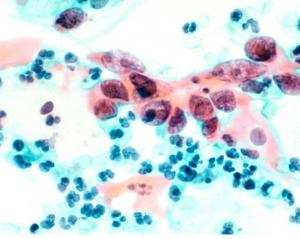

LE CANCER DU COL DE L’UTÉRUS : UN CANCER ÉVITABLE

Avec une évolution lente, l’existence des lésions précancéreuses curables et un test de dépistage efficace (le frottis cervico-utérin), le cancer du col de l’utérus est un candidat idéal au dépistage.